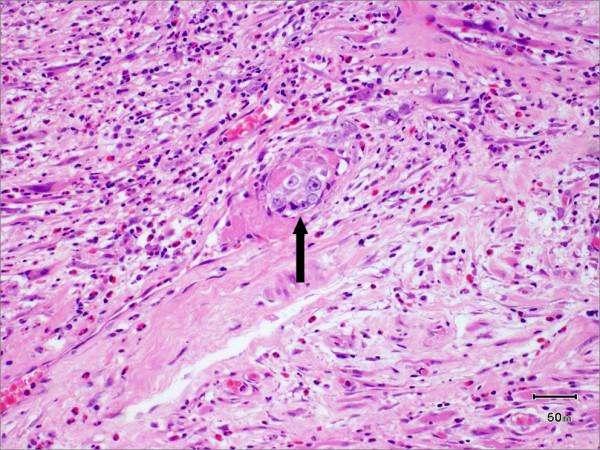

115例T1-T2期口腔鳞状细胞癌患者的临床病理参数、复发情况、局部区域及远处转移情况

Clinicopathological parameters, recurrence, locoregional and distant metastasis in 115 T1-T2 oral squamous cell carcinoma patients.

The incidence of oral squamous cell carcinoma remains high. Oral and oro-pharyngeal carcinomas are the sixth most common cancer in the world. Several clinicopathological parameters have been implicated in prognosis, recurrence and survival, following oral squamous cell carcinoma. In this retrospective analysis, clinicopathological parameters of 115 T1/T2 OSCC were studied and compared to recurrence and death from tumour-related causes. The study protocol was approved by the Joint UCL/UCLH committees of the ethics for human research. The patients' data was entered onto proformas, which were validated and checked by interval sampling. The fields included a range of clinical, operative and histopathological variables related to the status of the surgical margins. Data collection also included recurrence, cause of death, date of death and last clinic review. Causes of death were collated in 4 categories (1) death from locoregional spread, (2) death from distant metastasis, (3) death from bronchopulmonary pneumonia, and (4) death from any non-tumour event that lead to cardiorespiratory failure. The patients' population comprised 65 males and 50 females. Their mean age at the 1st diagnosis of OSCC was 61.7 years. Two-thirds of the patients were Caucasians. Primary sites were mainly identified in the tongue, floor of mouth (FOM), buccal mucosa and alveolus. Most of the identified OSCCs were low-risk (T1N0 and T2N0). All patients underwent primary resection +/- neck dissection and reconstruction when necessary. Twenty-two patients needed adjuvant radiotherapy. Pathological analysis revealed that half of the patients had moderately differentiated OSCC. pTNM slightly differed from the cTNM and showed that 70.4% of the patients had low-risk OSCC. Tumour clearance was ultimately achieved in 107 patients. Follow-up resulted in a 3-year survival of 74.8% and a 5-year survival of 72.2%. Recurrence was identified in 23 males and 20 females. The mean age of 1st diagnosis of the recurrence group was 59.53 years. Most common oral sites included the lateral border of tongue and floor of mouth. Recurrence was associated with clinical N-stage disease. The surgical margins in this group was evaluated and found that 17 had non-cohesive invasion, 30 had dysplasia at margin, 21 had vascular invasion, 9 had nerve invasion and 3 had bony invasion. Severe dysplasia was present in 37 patients. Tumour clearance was achieved in only 8 patients. The mean depth of tumour invasion in the recurrence group was 7.6 mm.An interesting finding was that 5/11 patients who died of distant metastasis had their primary disease in the tongue. Nodal disease comparison showed that 8/10 patients who died of locoregional metastasis and 8/11 patients who died from distant metastasis had clinical nodal involvement. Comparing this to pathological nodal disease (pTNM) showed that 10/10 patients and 10/11 patients who died from locoregional and distant metastasis, respectively, had nodal disease. All patients who died from locoregional and distant metastasis were shown to have recurrence after the primary tumour resection. Squamous cell carcinoma of the oral cavity has a poor overall prognosis with a high tendency to recur at the primary site and extend to involve the cervical lymph nodes. Several clinicopathological parameters can be employed to assess outcome, recurrence and overall survival.

口腔鳞状细胞癌的发病率仍然很高。口腔癌和口咽癌是全球第六大常见癌症。口腔鳞状细胞癌发生后,一些临床病理参数与预后、复发和生存率相关。在这项回顾性分析中,研究了115例T1/T2期口腔鳞状细胞癌的临床病理参数,并将其与肿瘤相关原因导致的复发和死亡情况进行比较。该研究方案已获得伦敦大学学院/大学学院医院人类研究伦理联合委员会的批准。患者数据被录入表格,并通过间隔抽样进行验证和检查。这些领域包括一系列与手术切缘状态相关的临床、手术和组织病理学变量。数据收集还包括复发情况、死亡原因、死亡日期和最后一次临床复查。死亡原因分为4类:(1) 局部区域扩散导致的死亡;(2) 远处转移导致的死亡;(3) 支气管肺炎导致的死亡;(4) 任何导致心肺功能衰竭的非肿瘤事件导致的死亡。患者群体包括65名男性和50名女性。他们首次诊断为口腔鳞状细胞癌时的平均年龄为61.7岁。三分之二的患者为白种人。原发部位主要位于舌、口底、颊黏膜和牙槽。大多数确诊的口腔鳞状细胞癌为低风险(T1N0和T2N0)。所有患者均接受了原发灶切除,必要时进行颈部清扫和重建。22例患者需要辅助放疗。病理分析显示,一半的患者患有中度分化的口腔鳞状细胞癌。pTNM与cTNM略有不同,显示70.4%的患者患有低风险口腔鳞状细胞癌。最终107例患者实现了肿瘤清除。随访结果显示3年生存率为74.8%,5年生存率为72.2%。23名男性和20名女性出现复发。复发组首次诊断时的平均年龄为59.53岁。最常见的口腔部位包括舌外侧缘和口底。复发与临床N分期疾病相关。对该组的手术切缘进行评估,发现17例有非粘连性浸润,30例切缘有发育异常,21例有血管浸润,9例有神经浸润,3例有骨浸润。37例患者存在重度发育异常。仅8例患者实现了肿瘤清除。复发组肿瘤浸润的平均深度为7.6毫米。一个有趣的发现是,11例死于远处转移的患者中有5例原发疾病位于舌部。淋巴结疾病比较显示,10例死于局部区域转移的患者中有8例以及11例死于远处转移的患者中有8例有临床淋巴结受累。将此与病理淋巴结疾病(pTNM)进行比较显示,分别死于局部区域和远处转移的10例患者和11例患者中有10例有淋巴结疾病。所有死于局部区域和远处转移的患者在原发肿瘤切除后均出现复发。口腔鳞状细胞癌总体预后较差,在原发部位复发和累及颈部淋巴结的倾向较高。可以采用一些临床病理参数来评估预后、复发和总体生存率。